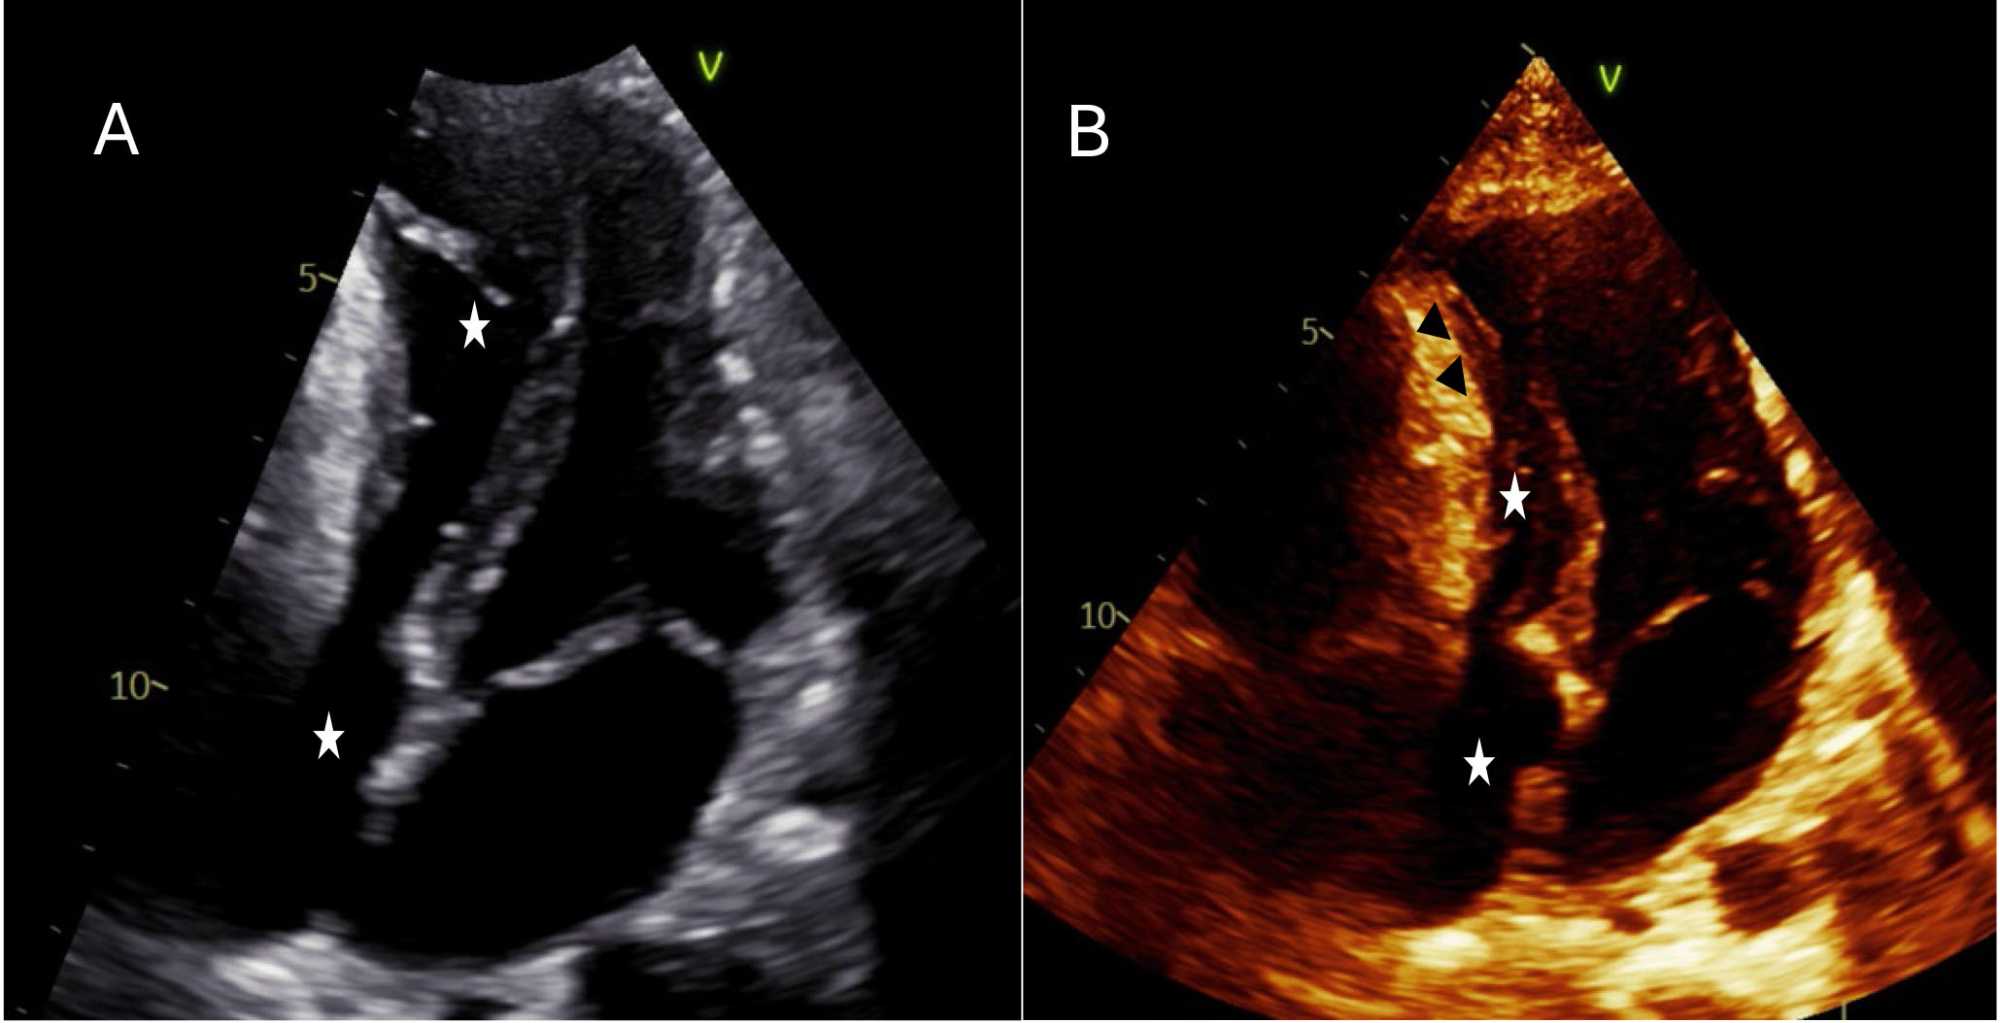

An echocardiogram was performed to confirm the relation and the connection of the mass with cardiac chambers. It showed normal left ventricular (LV) cavity dimensions with normal LV function. Externally, a large cystic mass was present anteriorly, compressing both the right atrium (RA) and right ventricle (RV), and causing turbulence at mid-RV level. The left lateral and anterior pericardium was bright and echogenic (Figure 2).

Figure 2. Panel (A-B) Transthoracic echo four chamber apical view shows the compressive effect of the cyst on the right side of the heart resulting in slit like right ventricle and right atrium (white stars). Panel (B) hyperechoic cyst wall lateral to the midbasal and midapical RV free wall (Black arrowheads).